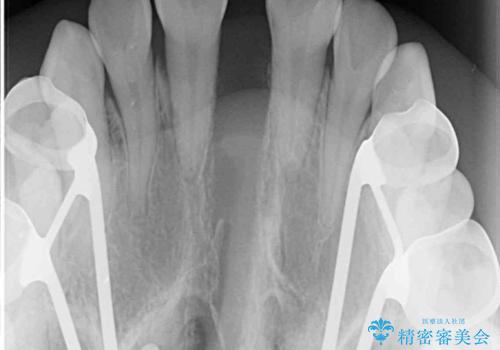

- 前歯の開咬と、受け口による咬み合わせの悪さを気にして来院された患者様です。

上顎歯列が狭窄していたため、急速拡大装置により上顎骨を側方に拡大し、その後ワイヤー装置にて矯正治療を行うこととしました。

舌の突出癖が開咬の原因であったので、改善のための舌トレーニングを行っていただきました。

舌トレーニングは後戻りにも大きく影響するため、とても重要なトレーニングです。